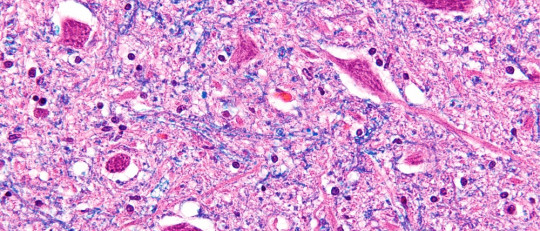

Quizá suene muy obvio, pero el carácter diferencial principal entre ambas condiciones se encuentra en su propio nombre. Tal y como indica el término, la gastritis hace referencia a la inflamación aguda o crónica de la mucosa gástrica. No cabe duda, por tanto, de que esta entidad clínica se circunscribe al entorno del estómago.

Se estima que ⅔ de la población están infectados por esta bacteria, que con su forma de espiral y su flagelo, es capaz de taladrar la mucosa gástrica y dañar de forma lenta pero constante al epitelio del estómago. Por esta razón, este microorganismo se ha asociado con diversas patologías a nivel gástrico.

El 70% de las infecciones por H. pylori son asintomáticas, pero el 30% restante de los individuos afectados desarrollan síntomas de gastritis, que a su vez se pueden acompañar de úlceras pépticas e incluso cáncer de estómago. Sin ir más lejos, se estima que las personas con esta bacteria en su estómago son el doble de proclives a desarrollar una úlcera a lo largo de su vida, en comparación con aquellas que no la presentan.